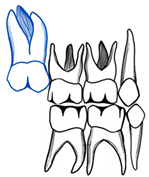

| Barberia-Leache ’s Classification (Based on the effect on second primary molar) * | |||||

| Grade 1 Mild | Grade 2 Moderate | Grade 3 Severe | Grade 4 Very severe | ||

| Limited resorption to the cementum or with minimum dentine penetration | Resorption of the dentine without pulp exposure | Resorption of the distal root leading to pulp exposure | Resorption that affects the mesial root of the second primary molar | ||

![]() | ![]() | ![]() | ![]() | ||

| Harrison and Michal’s Classification (based on severity of the lock using bitewing radiograph) * | |||||

| Normal | Minimal lock | Severe lock | |||

| No sign of impaction | Impacted less than half the width of the distal marginal ridge of the second primary molar | Impacted more than the width of the distal marginal ridge of the second primary molar | |||

![]() | ![]() | ![]() | |||